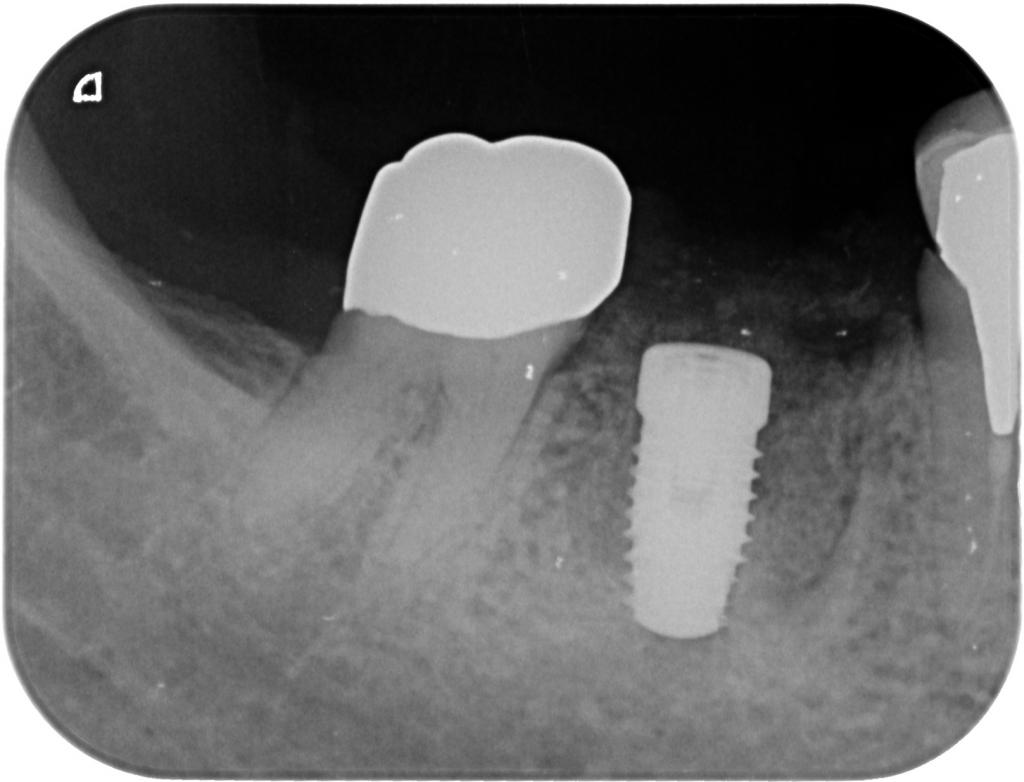

- インプラント埋入後のレントゲン写真です。

適切な位置、方向に埋入されています。

- 術後のレントゲン写真です。